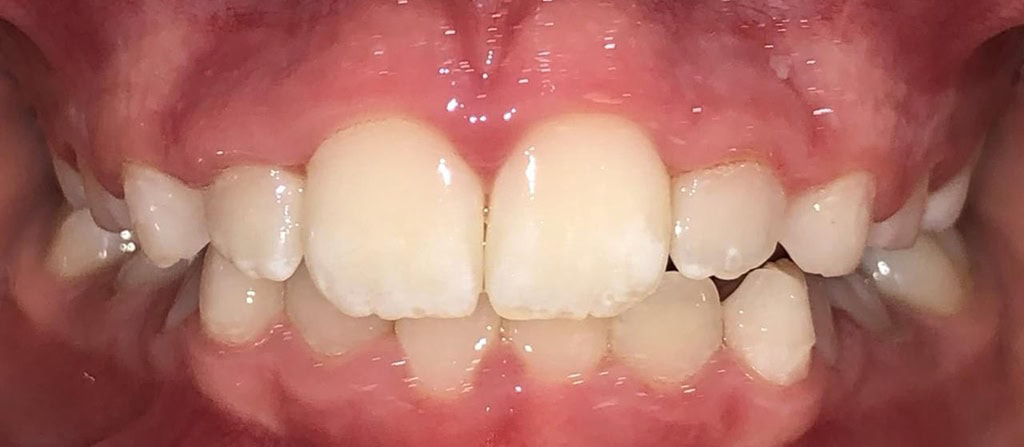

Actual Patient: Bailey

Before

Severe “Overbite”, BUCK TEETH, Narrow Jaws, Severe Deep Bite

Front View